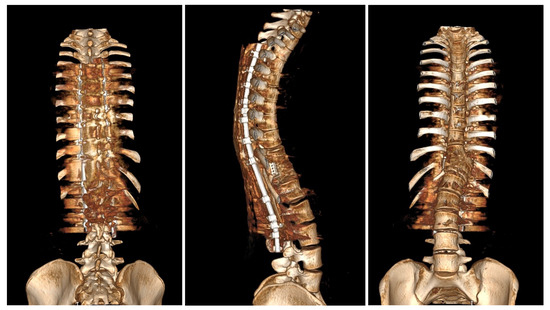

Neurological examinations showed full strength (5/5) in all major muscle groups of BUE/BLE, sensation intact throughout, normal reflexes (including abdominal), and pain on palpation in the thoracic spine above and below the gibbous. The neuro-imaging findings indicated a Cobb angle of 63° in the main thoracolumbar curve. The flexibility of the curve was measured at 63° when bending, decreasing to 48°. Additionally, there was a thoracic kyphosis of 4° between T2 and T5 and 32° between T5 and T12, with a severe focal thoracic kyphosis of 108° (Figure 2).

Figure 2. Standard standing AP and lateral X-rays and side-bending films of the 16-year-old female before surgical treatment. These X-rays showed severe and stiff congenital kyphosis.